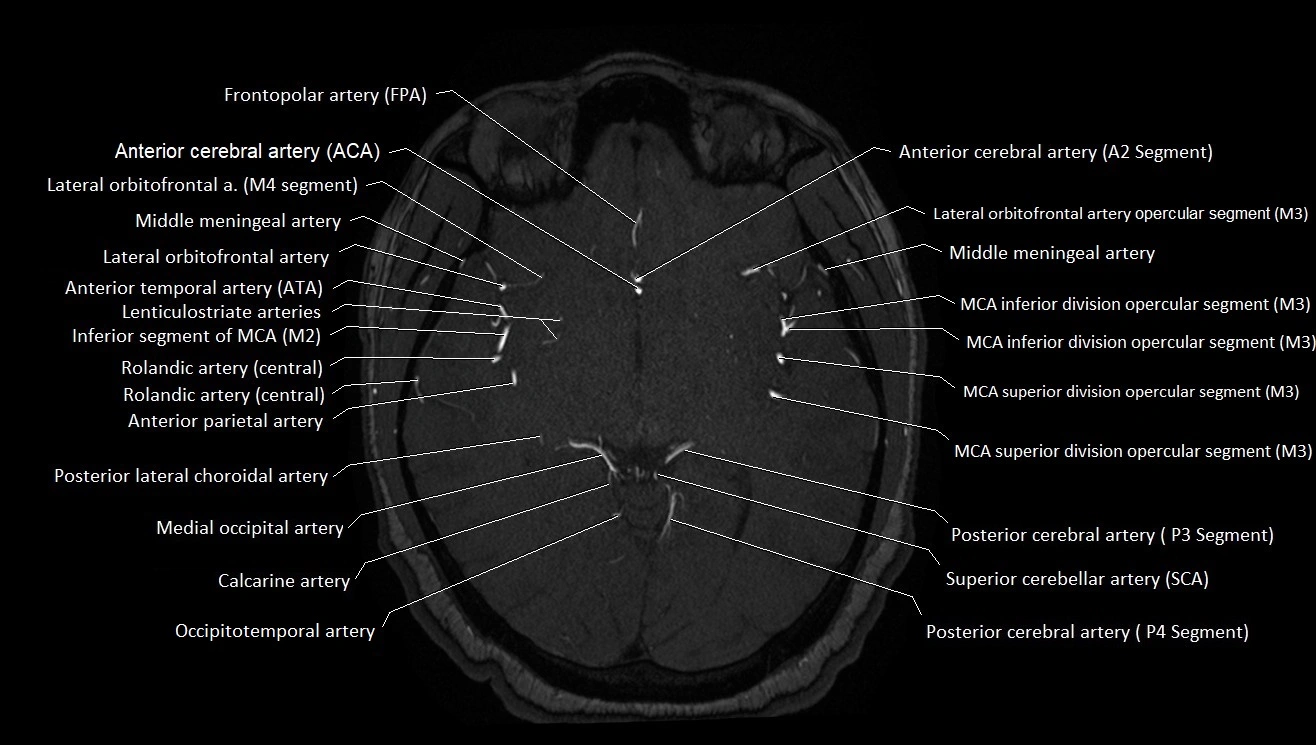

MRA (Magnetic Resonance Angiography):

• Flow-related enhancement makes the AChA appear as a bright, linear vascular signal against suppressed background

• High sensitivity for origin and proximal course; distal branches may be too small to resolve

• Detects stenosis, occlusion, aneurysm, AVM feeders

MRI images

image